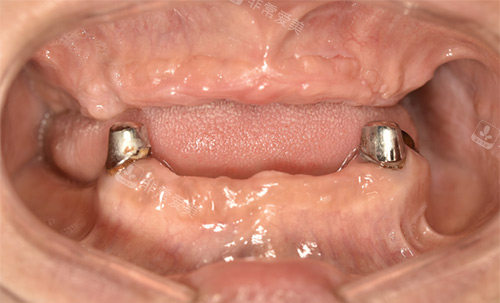

穿颧穿翼种植拍片

顾客做高难度种植后反馈如何?

真实的顾客反馈较有说服力,不少在凯尔口腔找牛凯医生做过高难度种植的顾客,都给出了好评。

张阿姨(全口缺牙,all-on-4种植):“我缺牙10多年,戴活动假牙总掉,吃东西没味道。

牛医生说我骨量不够,推荐all-on-4,当天种完就戴上了临时牙,现在能吃包子、面条,比以前舒服太多了!”

王先生(骨量重度不足,穿颧种植):“之前去别的医院说要植骨,改善期太长,后来听说凯尔口腔牛医生能做穿颧种植,不用植骨。

手术很顺利,现在种完半年了,牙齿用着跟真牙一样,感谢牛医生!”